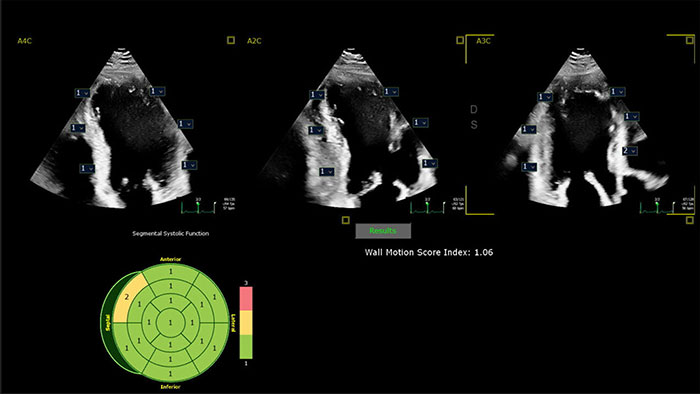

Philips AI-based ultrasound solutions integrate into everyday clinical workflows and are designed to make it easier and faster for clinicians to acquire, select, measure and report accurate results.